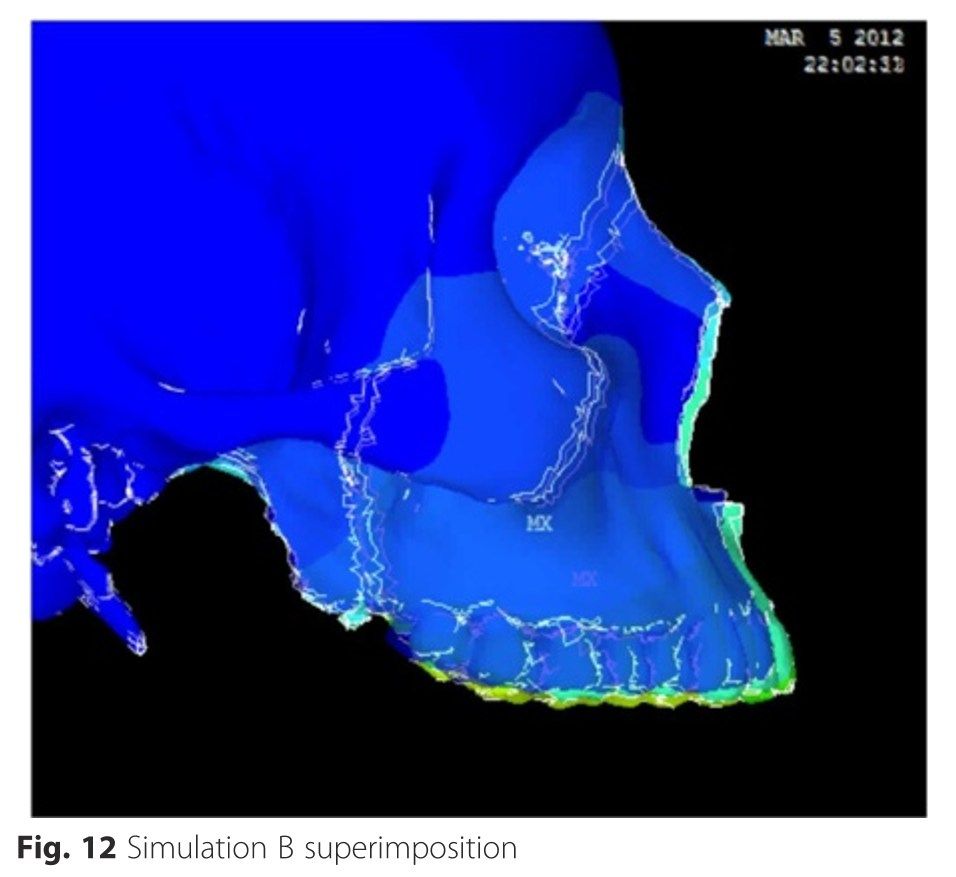

From this paper this is the typical maxilla displacement resulting from a microimplant assisted palate expander like MSE, Hyrax using a facepuller at a -30 degrees angle:

Look at how insignifiant is the forward displacement and how it displace your maxilla downward.